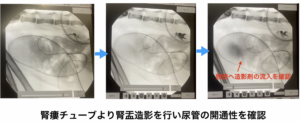

• 右側:尿管膀胱新吻合術(ureteroneocystostomy)を実施し、術後の尿流確保を目的として腎瘻チューブ設置

術後の経過は良好で、術後5日目に右腎瘻チューブより腎盂造影検査を実施したところ、尿管の開通性が確認できたため、腎瘻チューブを抜去した。